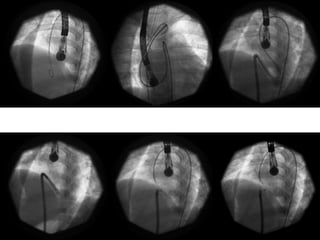

Device selection

 Type of the device

 Size of the device

Determinants of the Device type

 Size of the defect

 Morphology of the defect

Size of the defect

 ADO II : upto 5.5 mm

 Nit Occlud Le VSD coil : upto 8 mm

 ADO I : upto 12 mm

 AAPMVSDO & AMVSD occluder : upto 16 mm

 Modified Membranous VSD occluders

(Lifetech and Shanghai Steel Corp) : upto 19

mm

Sizing the device

 No definite guidelines

 Echo Vs Angio

 LV Vs RV

 APMVSDO: RV side of the defect. Measure in

two planes. Average and add 1

 ADO I: RV side of the defect + 1 or 2 =

Pulmonary end of the ADO I

 ADO II: RV side of the defect + 0.5 to 1 mm